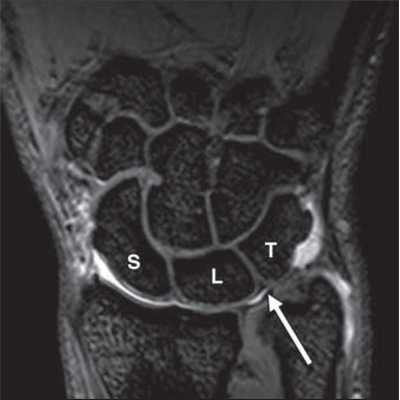

МРТ кисти. Корональная градиентная МРТ. Нормальное изображение полулунно-трехгранной связки. Обозначения: S – ладьевидная кость (scaphoid), L – полулунная кость (lunatum), T- трехгранная кость (triquetrum).